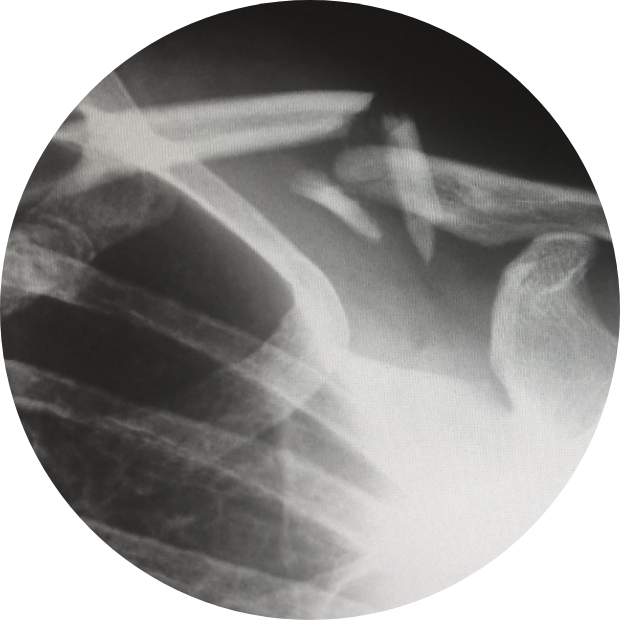

Consecinte ale fracturilor netratate

Traumatologie sportivă

Categorii de risc pentru fracturi De cele mai multe ori, fracturile apar in urma unui